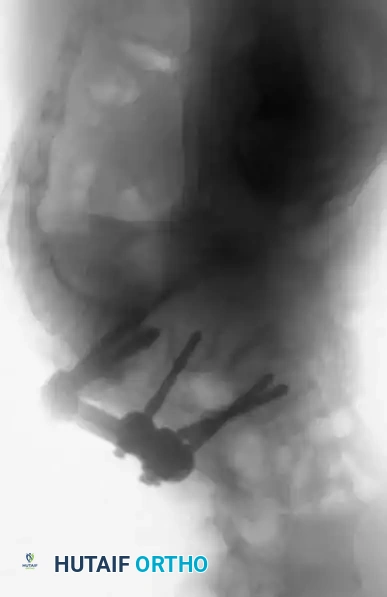

Surgical Pitfall: In severe dysplastic slips, the anatomy is grossly distorted. The L5 lamina

Associated Surgical & Radiographic Imaging